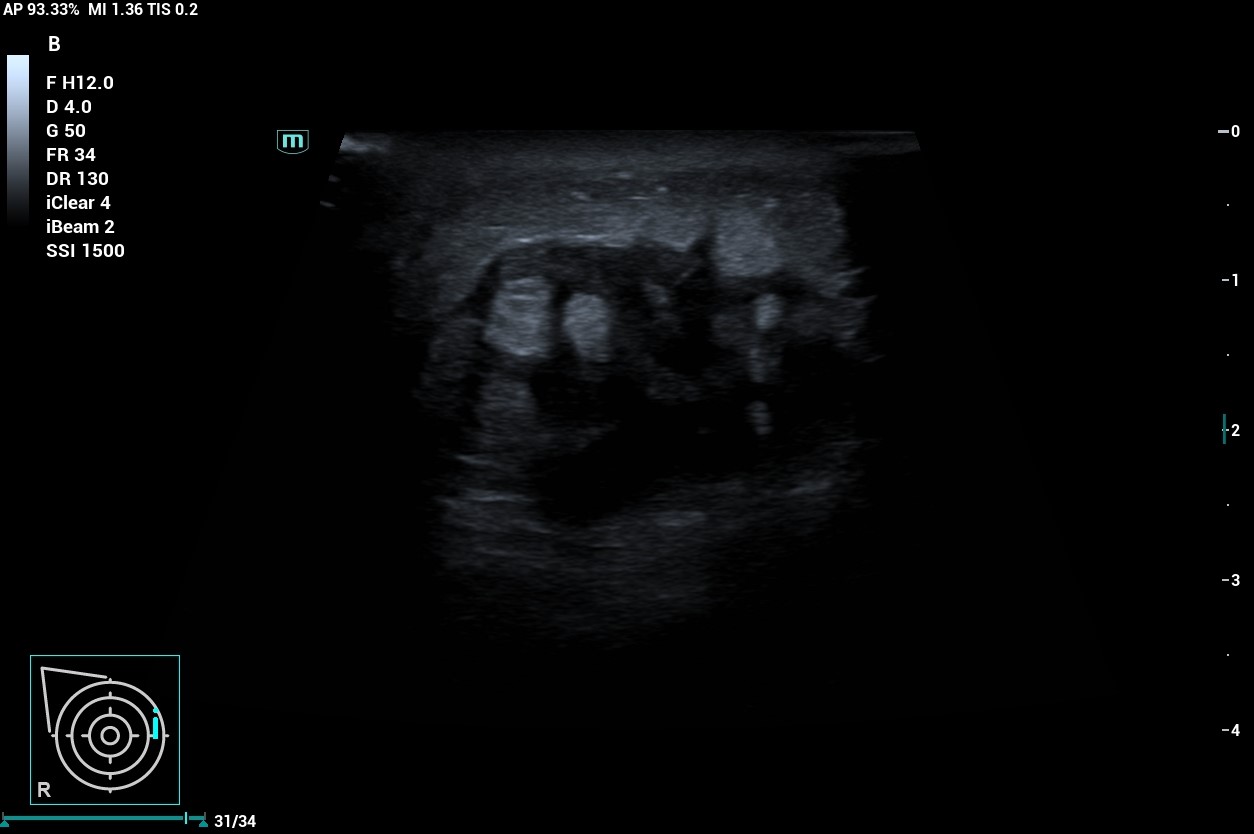

Al realizar ecografía observamos una imagen de 30 mm en cuadrantes internos de mama derecha que presenta bordes espiculados y contenido heteroecoico en su interior con áreas hipoecoicas.

Al tratarse de una lesión que presenta características de probable malignidad no solo en la exploración y anamnesis de la paciente sino a la confirmación con la ecografía, decidimos derivar a la paciente a Ginecología mediante circuito rápido, donde se confirma el diagnóstico de carcinoma ductal infiltrante de mama derecha G2, luminal B cT4bN3bM0.